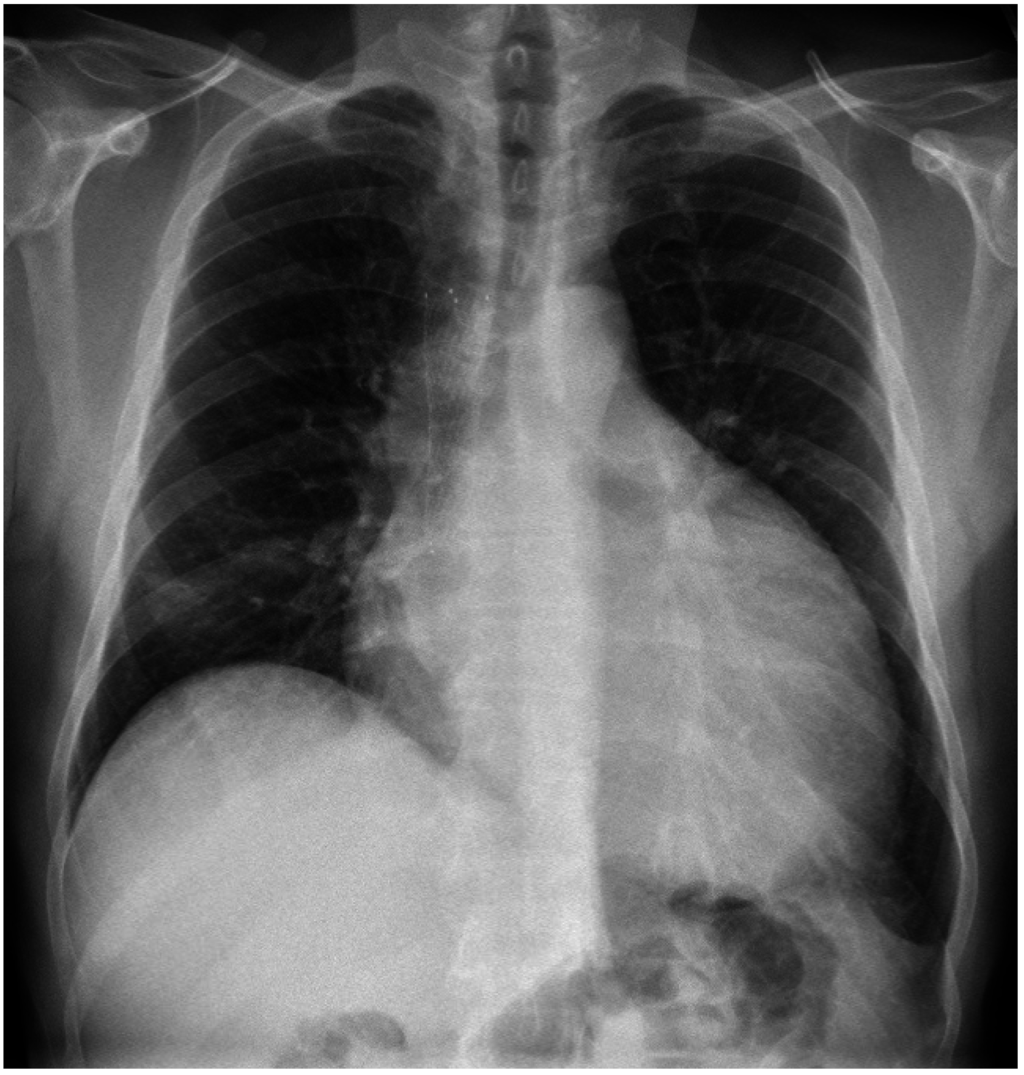

2. Case 1